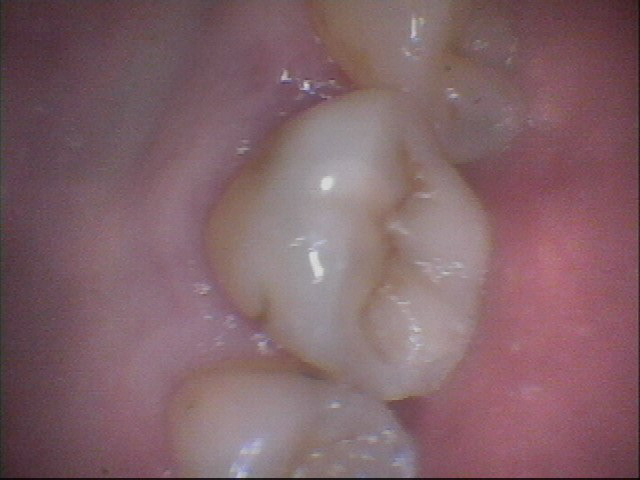

26 - 27 Pre-op